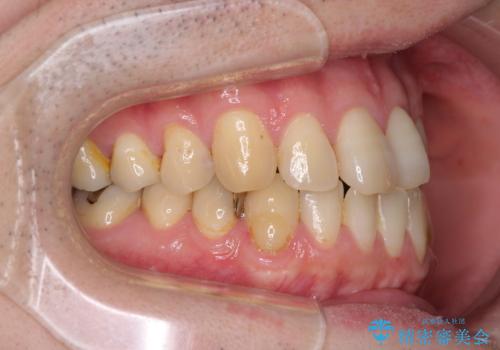

左上の犬歯が欠損しているため、正中の位置や奥歯の咬み合わせが理想的にならない点を了承していただきました。

インビザライン矯正は、1日22時間を目安に装着する必要がありますが、しっかりと装着してくださったので、順調に治療を進めることができました。